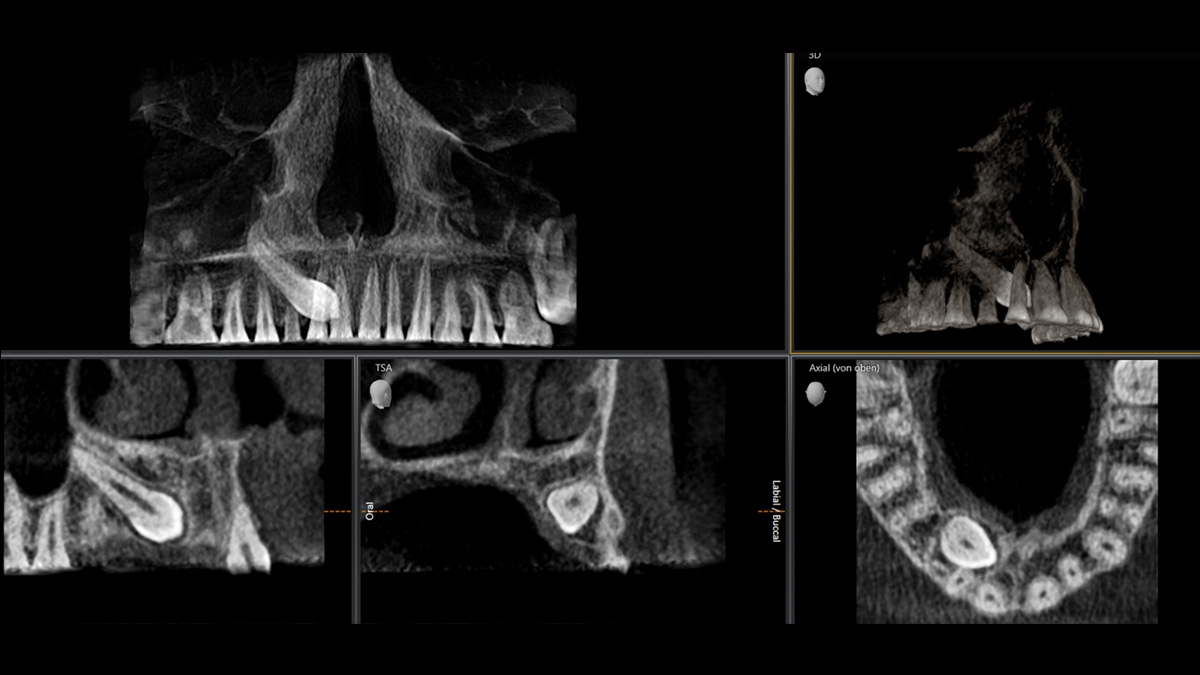

Gallery of Sample 3D Images

5 cm x 5.5 cm Low Dose volume, 3 μSv, displaced tooth case